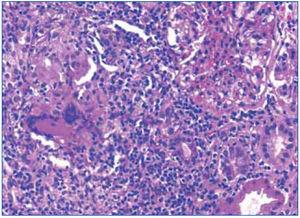

Ante los hallazgos clínicos (insuficiencia renal grave), los hallazgos radiológicos (riñones de tamaño y ecoestructura normales) y los hallazgos analíticos (anemización, proteinuria y microhematuria), se realizó una biopsia renal en la que se detectó una inflamación intersticial a expensas de linfocitos, acompañados de histiocitos que en varios puntos formaban granulomas (figura 3 y figura 4). En uno de ellos existían células gigantes multinucleadas de tipo Langhans. Los glomérulos fueron normales. En los túbulos, había ocupación de la luz con material granular y aplanamiento del epitelio. No se observaron microorganismos en las tinciones de PAS y de Ziehl-Nielsen.

Figura 3. Infiltrado linfocitario intersticial y un granuloma epitelioide en la biopsia renal.